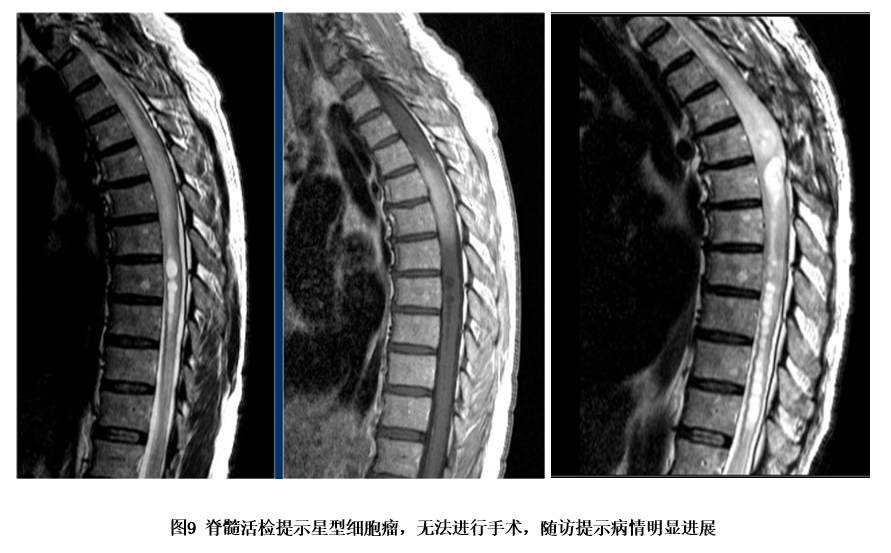

以中胸段或下胸段多见,脊髓核磁可发现以前角为中心的长t1

图片尺寸851x589